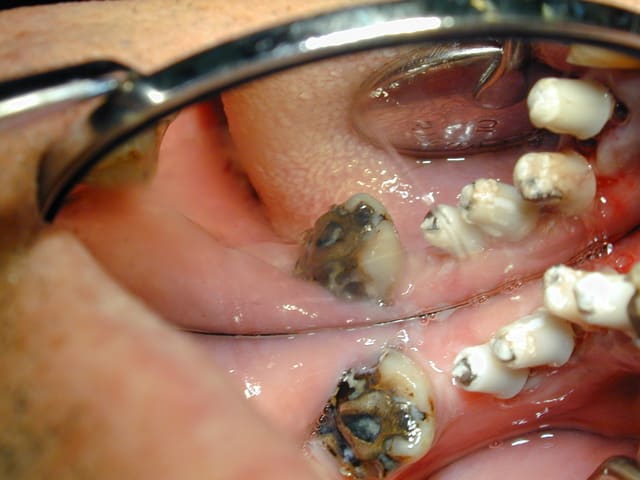

Dscn4996 ifkj7r - Eugenol

Dscn5000 iwkei5 - Eugenol